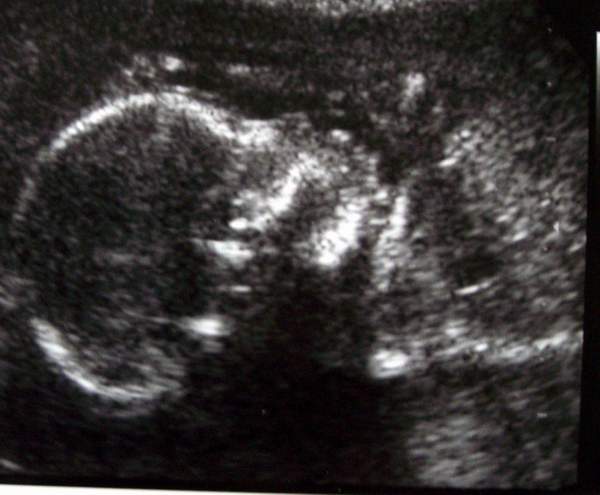

Igen, ma voltunk UH-n. Na hát, mint minden kismama tök szuperül elsírtam magam uh közben :) csak úgy potyogtak a könnyeim. Nagyon édes volt :) megfogta a kis lábacskáit a kezeivel, aztán jó nagyon ásított, megvakargatta a kis fejét :) szóval alkotott, meg persze a lábait keresztbe tette, de nem vagyok szomorú, hogy nem tudtuk meg, hogy mi lesz, majd legközelebb :) Egyébként minden rendben van BPD: 45 mm, s 40-50 mm között kell lennie. Az uh-s doki mondta, hogy mindent rendben lát, a kis szivecskéje is jól működik, a vesék is, a pisilés is megy neki :) mindent szuperül lehetett látni, pedig nem 4D-s volt. 2 kép készült, az egyik egész jó lett, majd azt felteszem,s ideje lenne már egy 19 hetes pocifotónak is :wink:

Kép 19. hetes UH

Én tegnap voltam újabb kb. 1,5órás uh-n, mindent összevetve ennyi volt a dokival töltött idő. Megnézte mind a két babót, képet ide nem teszek, a blogba bent lesz nézzétek meg. Mondjuk sokat nem lehet látni, sajnos az arcát nem akarta megmutizni nekünk, de........ az egyik babóca lány a másik fiú mint ahogy eddig is volt vagyis a 12hetesen már kiderült.

BPD: kiscsajnál 42mm kispasinál, 42,6mm a többi adatot nem írom van még egy csomó :) becsült súly nem volt és tejes hossz sem. Annyit mondott nagy babák a korukhoz képest.